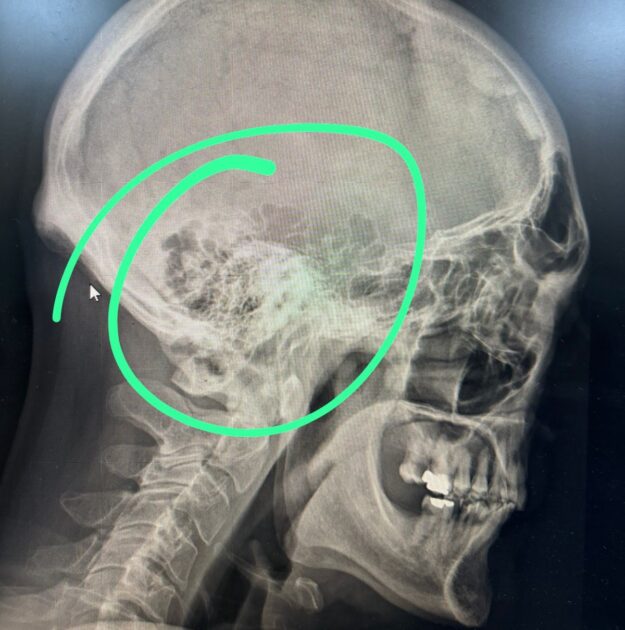

Tras esto, fue derivado a un Cesfam, aun con pérdida de memoria, por lo que luego fue dirigido al Hospital de Coquimbo, para que le realizaran un escáner de urgencia.

“Estuve un día completo en el hospital y me dieron el alta el viernes. Gracias a Dios, el escáner arrojó solo un TEC cerrado sin compromiso. Ahora estoy en casa recuperándome, más con susto que otra cosa”, acotó.